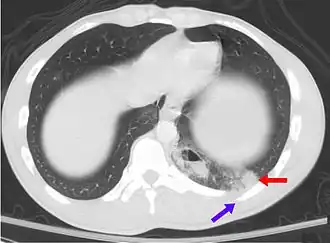

| Uma tomografia computadorizada mostrando uma contusão pulmonar (seta vermelha) acompanhada de uma fratura de costela (seta azul) | |